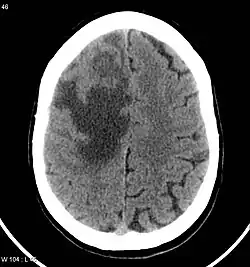

Imaging technology: MRI and CT scans

CNS metastases are diagnosed through imaging techniques that produce detailed images of the inside of the body, including parts such as the bones, organs, muscles, and nerves.[13] Magnetic resonance imaging (MRI) and computed tomography (CT) are two representative imaging procedures for this purpose.[12]

MRI scans use strong magnetic fields and radio waves to create an image, while CT scans use X-rays. MRI scans produce more detailed images of bodily structures, particularly soft tissues including the brain,[13] and are better at detecting CNS metastases than CT scans. However, CT scans are sometimes used for the initial imaging modality due to their lower cost and efficiency in screening for multiple conditions.[14]